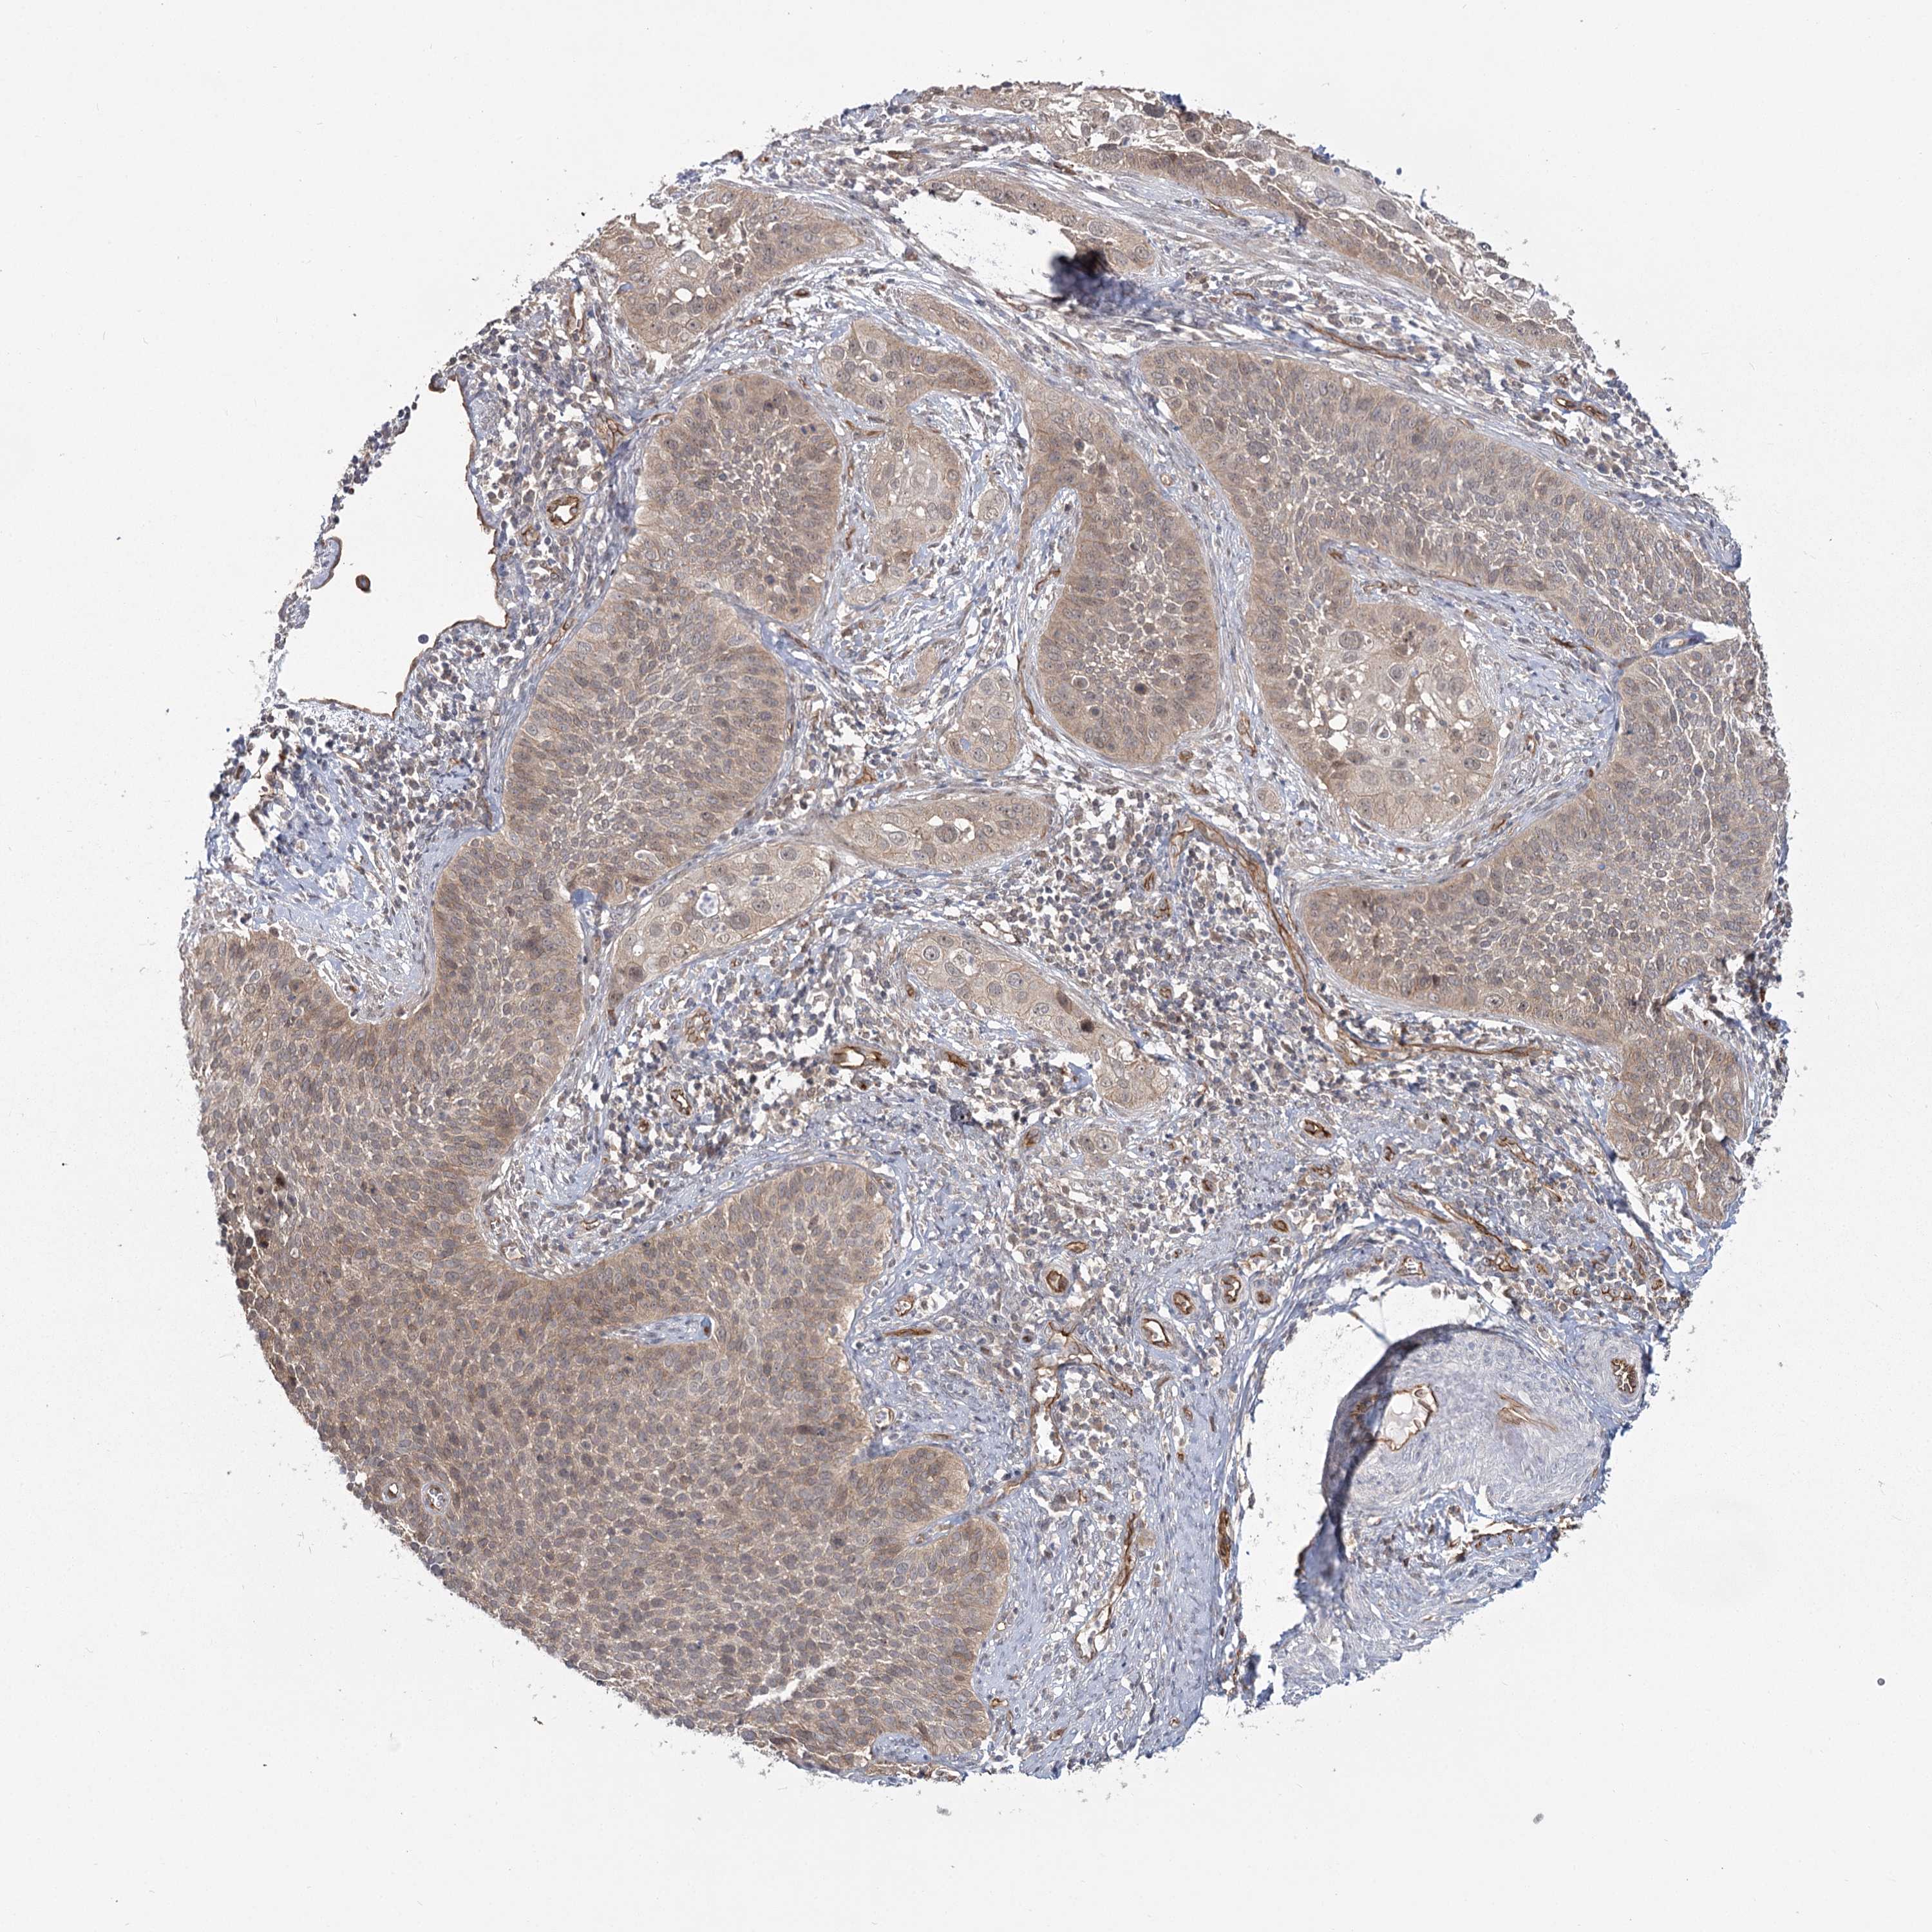

CERVICAL CANCER - Protein expressioni

A mouse-over function shows sample information and annotation data. Click on an image to view it in a full screen mode. Samples can be filtered based on level of antibody staining by selecting one or several of the following categories: high, medium, low and not detected. The assay and annotation is described here.

Note that samples used for immunohistochemistry by the Human Protein Atlas do not correspond to samples in the TCGA dataset.

Antibody stainingi

Antibody staining in the annotated cell types in the current human tissue is reported as not detected, low, medium, or high, based on conventional immunohistochemistry profiling in selected tissues. This score is based on the combination of the staining intensity and fraction of stained cells.

Each image is clickable and will lead to virtual microscopy that enables deeper exploration of all samples and also displays staining intensity scores, fraction scores and subcellular localization as well as patient and tissue information for each sample.

Antibody HPA036194

Staining

High

Medium

Low

Not detected

Intensity

Strong

Moderate

Weak

Negative

Quantity

>75%

75%-25%

<25%

None

Location

Nuclear

Cytoplasmic/membranous

Cytoplasmic/membranous,nuclear

Squamous cell carcinoma, NOS

Adenocarcinoma, NOS